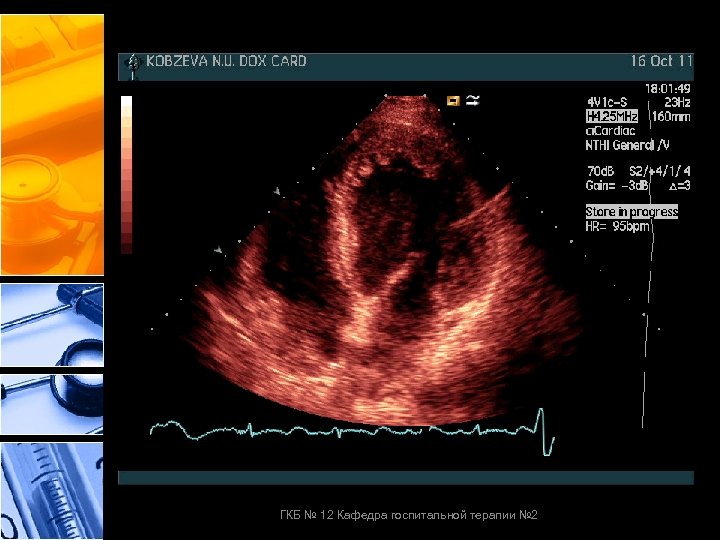

До химиотерапии После химиотера ГКБ № 12 Кафедра госпитальной терапии № 2

До химиотерапии После химиотер ГКБ № 12 Кафедра госпитальной терапии № 2

ГКБ № 12 Кафедра госпитальной терапии № 2